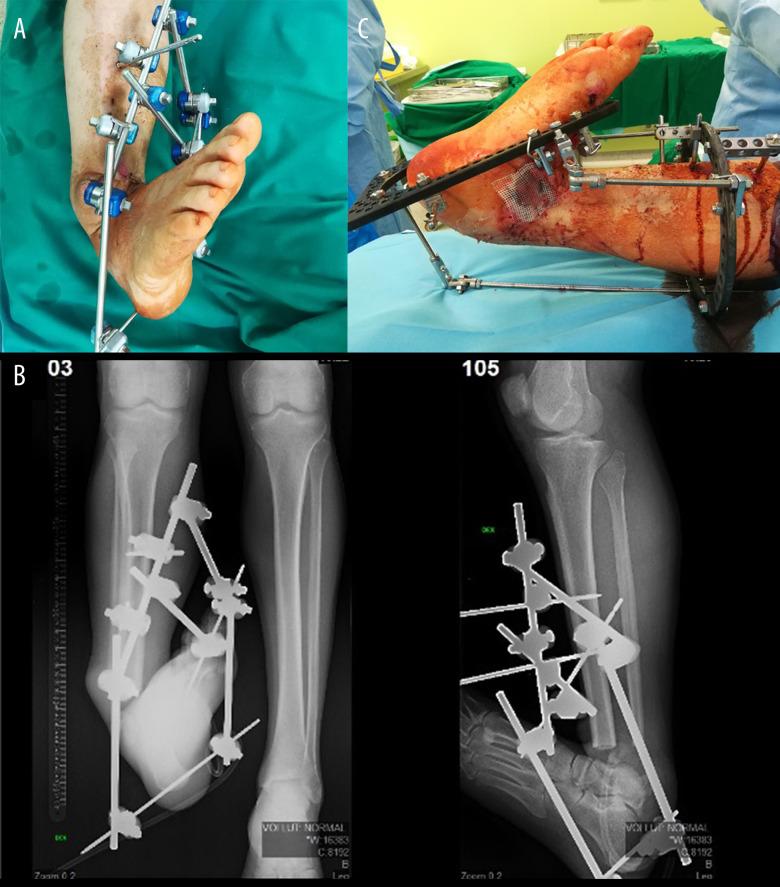

BACKGROUND In this case report, an alternative way of treating Gustillo-Anderson IIIB type fractures with severe soft-tissue damage is provided for cases where, for various reasons, it is not possible to close a soft-tissue defect with a flap. CASE REPORT An artificial deformity-creating technique was applied for a patient with a right distal tibial open fracture (Gustillo IIIB type) with complete tibial cartilage and bone loss of 10 cm and severe soft-tissue defect after high-energy trauma. This technique includes damaged limb shortening, translation, angulation, and rotation for closure of soft-tissue defects using orthopedic hexapod and bifocal bone transport without need for plastic surgery. Because of the timely planning and application of the orthopedic hexapod for the artificial deformity correction, the final alignment of the limb was close to the physiological standard and had good functional outcomes. Despite the extremely severe shortening and acute angles, the total treatment time was only 75 weeks. At the 1-year follow-up after treatment completion, the patient had good functional outcomes with the 36-Item Short Form Survey score: general health, 80%; physical functioning, 85%; and social functioning, 100%. CONCLUSIONS In conclusion, we show that the artificial deformity-creating with subsequent orthopedic hexapod application and lengthening of a limb is a robust method that can be applied even for the treatment of severe open fractures with significant soft-tissue damage and bone loss, which can be performed outside high-level trauma hospitals and has good clinical outcomes without significant complications.